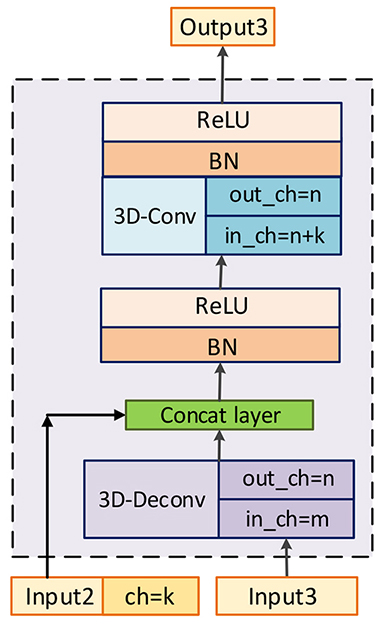

The purpose of fusion block is to effectively recalibrate and fuse low-level features from different modalities of MRI before merging them with high-level features. It is a hard task to directly fuse low-level features from multiple MRI, which vary greatly from each other due to the varied responses to different tissues of multi-modality MRI. Therefore, the fusion block will firstly re-weighting features and highlight regions that are greatly relevant to NPC with the assistance of 3D-CBAM. 3D-CBAM is composed with a channel attention block, which focuses on ’what’ are meaningful features, and a spatial attention block, which focuses on ‘where’ is an interesting part. After recalibrating low-level features, an RFBlock is utilized to fuse them into ones with the same channel number of corresponding high-level features to keep balance between them. The architectures of them are shown in Figure 4.

We denote as element-wise multiplication, which will automatically broadcast spatial attention weights () and channel attention weights () to fit input feature maps. Meanwhile, and are denoted as feature maps after being refined by channel attention block and spatial attention block respectively. is the final output, which is fused and refined by residual fusion block.

Channel attention block. The focus of channel attention block is to selectively emphasize feature maps, which are meaningful for final predictions. SENet [31] utilizes global average pooling to capture average-values of each feature map, and feeds them into a MLP to get weights for every channel. Compared to SENet, the channel attention block of CBAM [32] uses global max-pooling layers to get max-values of feature maps in additional to capturing average-values using global average-pooling layers. And both average-values and max-values are fed into a shared MLP. Then, the output vectors are combined by add operation.

In this paper, in order to better represent the global features for 3D medical images, we capture stds of every three-dimension features and combine them with average-values and max-values to produce weights for every channel feature. We denote obtained stds, average-values and max-values as . In terms of MLP, because there exist great gaps among the distribution of stds, average-values and max-values, we respectively set three MLPs for them. All of these MLPs are composed with one hidden layer setting hidden activation size as , where is the reduction ratio and we set in our experiments. And the final output channel weights has values for each channel feature. The formulation for is shown as followed:

| (7) |

| (8) |

| (9) |

| (10) |

Where is the sigmoid activation to produce channel-wise weights ranged from 0 to 1. Figure 4(a) shows the architecture of channel attention block.

Spatial attention block. The purpose of spatial attention block is to utilize feature maps after channel-wise refining to obtain 3D spatial attention map (). On the basis of previous work of CBAM, we capture stds, average-values and max-values along the channel axis and concatenate them to generate three 3D feature blocks. And these features are fed into a 3D convolutional layer with sigmoid as activation to produce . Through element-wise multiplication, informative regions will be effectively highlighted. The architecture of spatial attention block is shown in Figure 4(b), and the process can be summarized as followed:

| (11) |

Where is denoted as one single convolutional layer with kernel size of and the number of output’s channels is 1.

Residual fusion block. After highlighting informative features and ROIs, a residual fusion block is constructed to fuse and refine low-level features. It is worth mentioning that the numbers of channels are for , while the corresponding high-level features, which is prepared to combine with fused features, only has channels. Therefore, in order to keep balance between low-level and high-level features, an convolutional layer with channel outputs is utilized to fuse feature maps and reduce channel number firstly. Then, a residual block [39] is adopted to refine feature maps. This block is composed with two convolutional layers, both of them have kernels and the first one is followed by a batch normalization layer and a ReLU layer. We can summary this process using following equations:

| (12) |

| (13) |

Where is feature maps after convolutional layer, and is denoted as convolutional layer followed by a batch normalization layer and a ReLU layer.